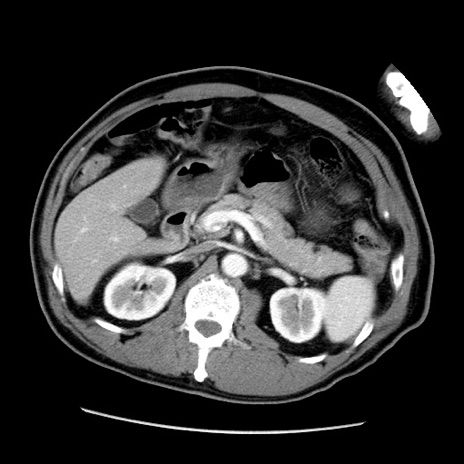

症例22(横断像)

【症例】50歳代男性

【主訴】腹痛

【現病歴】AVMからの被殻出血のため回復期リハ病棟入院中。 本日午後3時頃急に下腹部痛が出現した。

【既往歴】AVM、被殻出血、虫垂炎、高血圧

【身体所見】意識晴明、左半身不全麻痺、会話の理解は良好、36.5°C、腹部:膨隆、全体に板状硬、下腹部正中に圧痛点あり、反跳痛-、筋性防御不明、右下腹部にope scar

【データ】WBC 9400、CRP 0.06